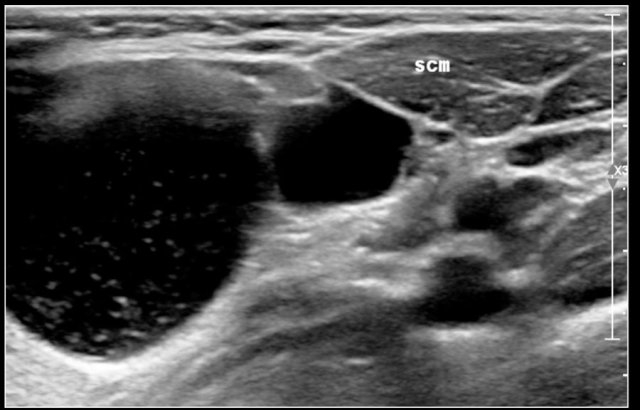

They are located along the anterior border of the sternocleidomastoid muscle, lateral to the common carotid artery, and if more cranially between the internal and external carotid artery.

Sometimes a beak sign may be seen as a curved rim of the lesion pointing medially between the internal and external carotid.

On ultrasound they often contains internal echoes caused by debris, which consists of cholesterol crystals.

Here another branchial cyst with a typical location superficial to the carotid artery bifurcation.